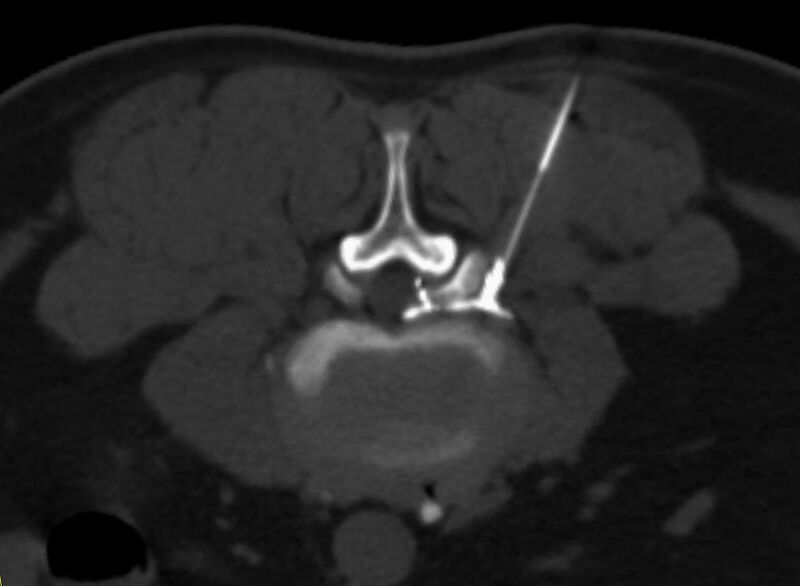

Wirbelsäule

• Darstellung von Frakturen, Tumoren und Bandscheibenveränderungen

Interventionelle Eingriffe

Durchführung am Standort im Diakonissenkrankenhaus

• z. B. Punktionen zur Gewebsentnahme

Schmerztherapie

Der Multislice-Scanner ermöglicht eine dem aktuellen Stand der Technik entsprechende, leitliniengerechte diagnostische Untersuchung sämtlicher Körperregionen. Darüber hinaus gestattet der neue Computertomograph auch eine für Arzt und Patient bequeme Durchführung CT-gestützter Interventionen wie z.B. Schmerztherapien der Wirbelsäule.